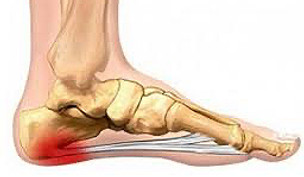

Aponévropathie plantaire

Motif de consultation :

Douleur sous le pied, particulièrement au talon, ressentie au lever ou après une activité prolongée.

Objectif de la prise en charge : Réduction de l’inflammation, étirement du fascia plantaire, et amélioration de l’appui plantaire. Modifications posturales si nécessaire.